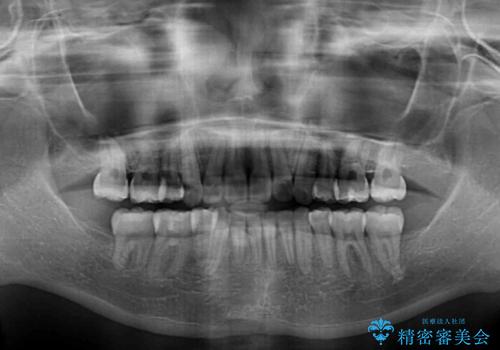

治療前の上下正中はずれていましたが、骨格的な上下左右差はあまり認められなかったため、正中を揃えて治療を終えることができました。

1年半ほどで治療を終えることができるとは我々も想像しておらず、患者様には大変満足していただきました。